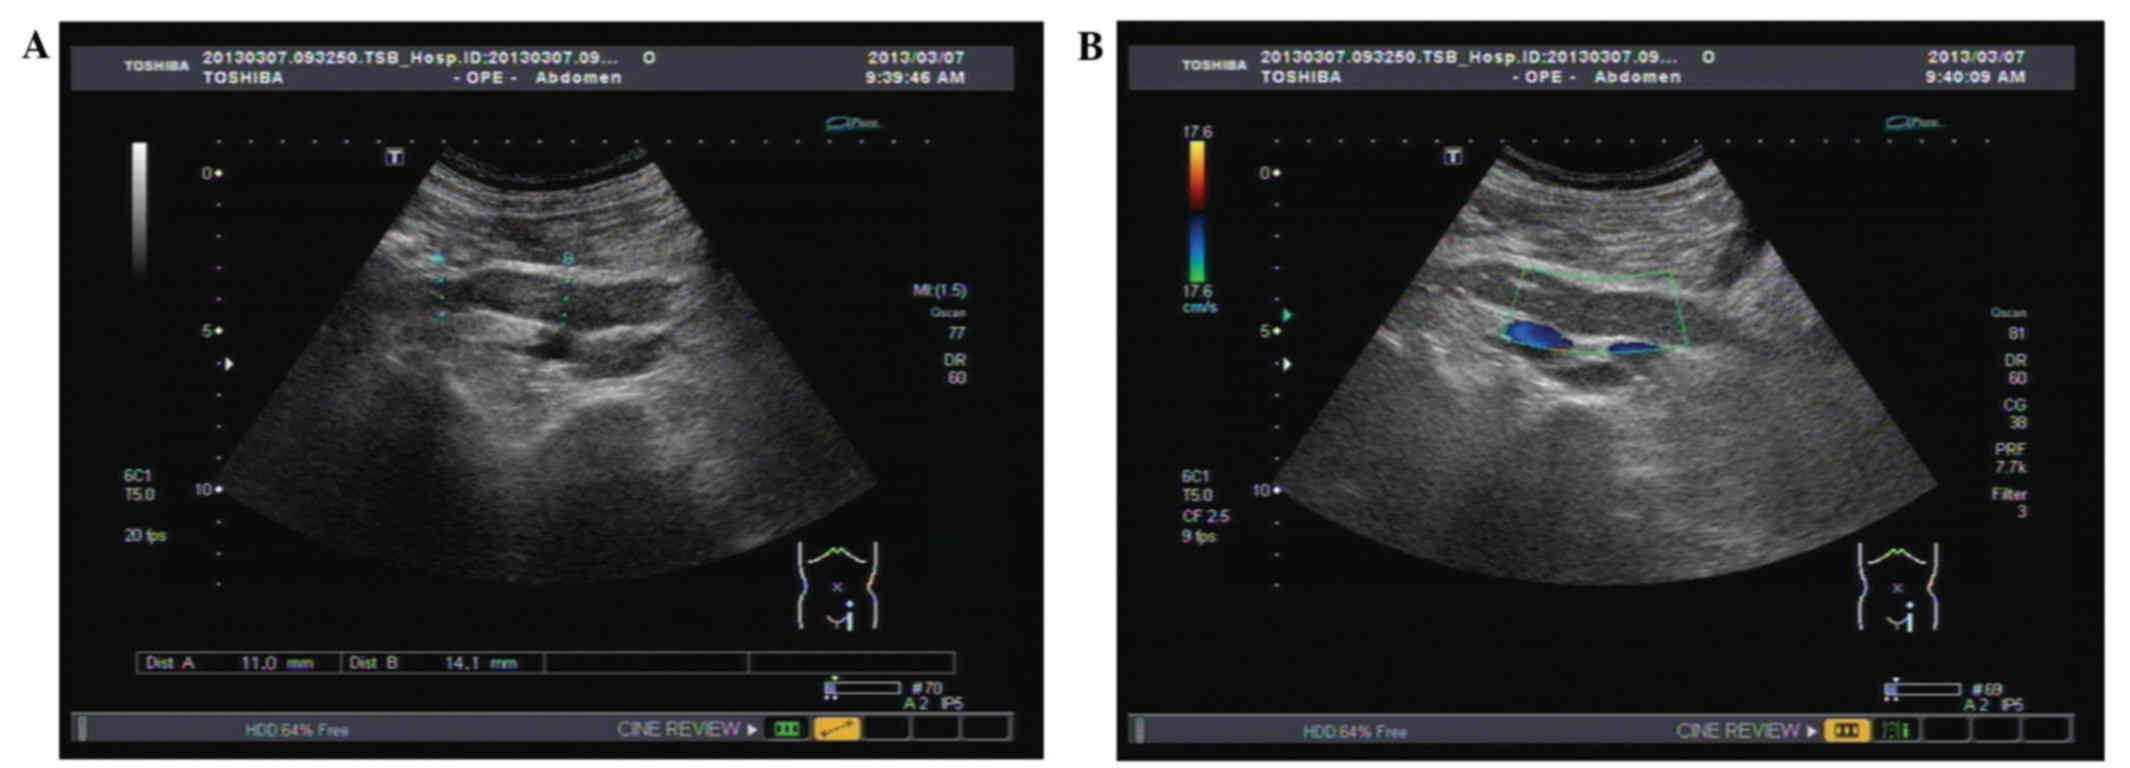

Figure 1

Figure 2

Figure 3